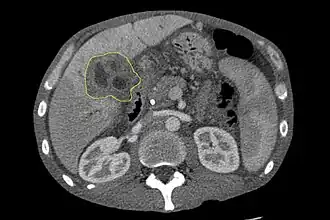

Компьютерная томография печени с холангиокарциномой | |